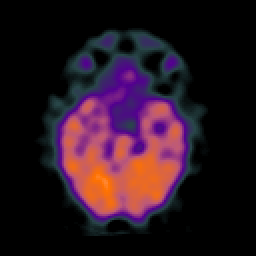

SPECT TC Study #6 -- Slice #20

[Home][Help][Clinical][Tour 1][Tour 2][Tour 3] Slice 20